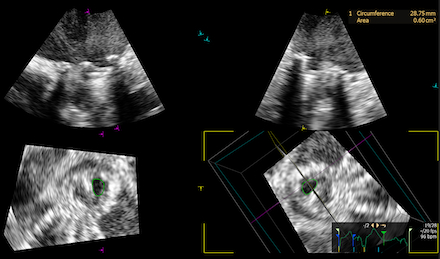

A 66 year old female with past medical history of rheumatic heart disease requiring mechanical mitral valve (MV) replacement on warfarin, HFpEF (EF 60%), atrial fibrillation requiring dual chamber pacemaker presented with worsening dyspnea on exertion. The patient was admitted for acute on chronic heart failure exacerbation requiring diuresis. Transthoracic echocardiogram (TTE) revealed significantly elevated gradients across the mitral prosthesis, concerning for significant prosthetic stenosis (peak velocity 2.4 m/s and mean gradient of 14 mmHg). Transesophageal echocardiogram (TEE) demonstrated moderate to severe mitral stenosis with a valve area of 0.6 sq cm by 3D planimetry, and poor leaflet excursion concerning for thrombus or pannus (Figure 1). Cardiac CT was suggestive of thrombus around the mechanical MV leaflets (Figure 2). Clinically, the patient had interval worsening heart failure symptoms and chest x-ray with worsening pulmonary edema. After consultation with cardiothoracic surgery, tPA was administered over 24 hours under close monitoring in the Cardiac Critical Care Unit. Repeat TEE post-thrombolysis showed improvement in MV area to 1.57 sq cm by 3D planimetry, with increased mobility of one mechanical MV leaflet (Figure 3). Persistent restriction of the other leaflet concerning for pannus remained, with no urgent surgical intervention indicated.